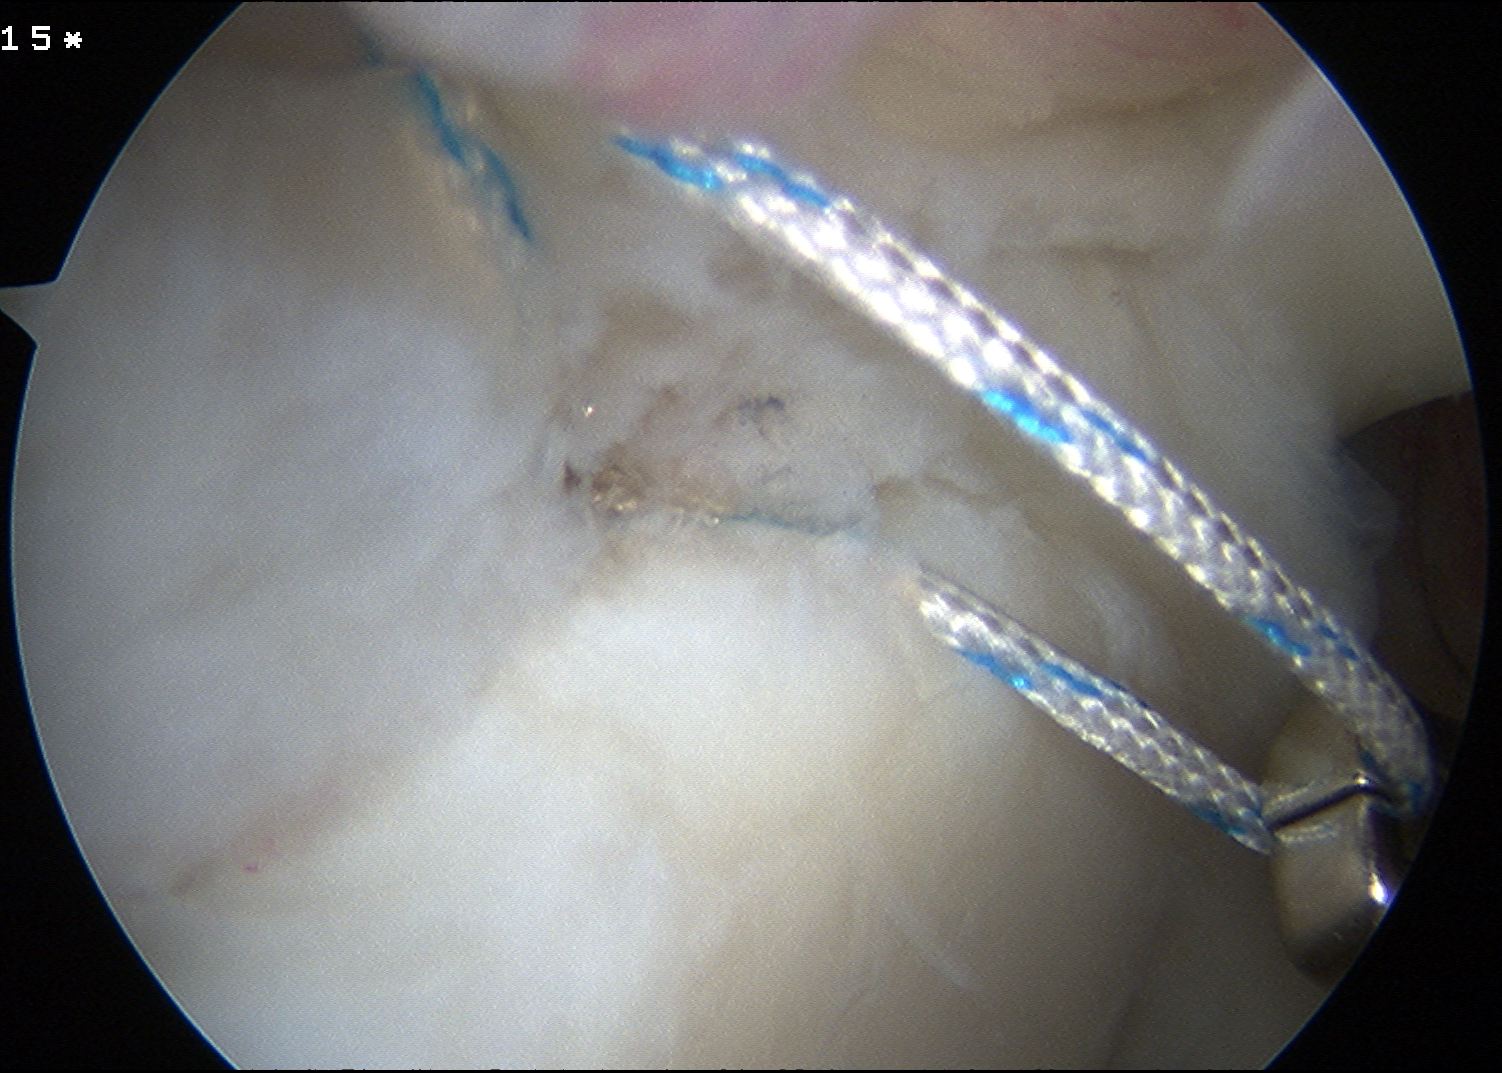

Anterior anchor

- best to pass the suture passer above the biceps to get good bite

- retrieve sutures and tie from port of Wilmington

Posterior 2 anchors

- pass suture passer under biceps